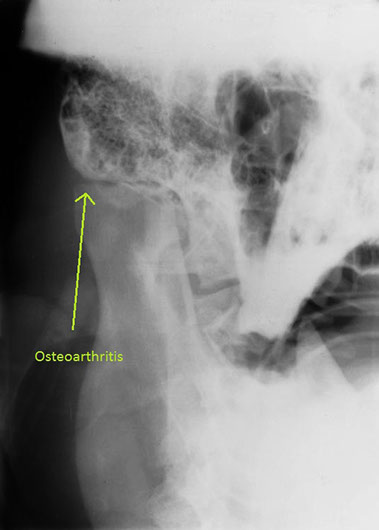

A radiograph of the mouth showed degenerative changes in the temporomandibular joint which is markedly narrowed and no evidence of a calculus which would be expected to be radio-opaque. Motaba was transferred to Werribee Zoo where he is still living and has a diet of soft food and no hard sticks to chew on.